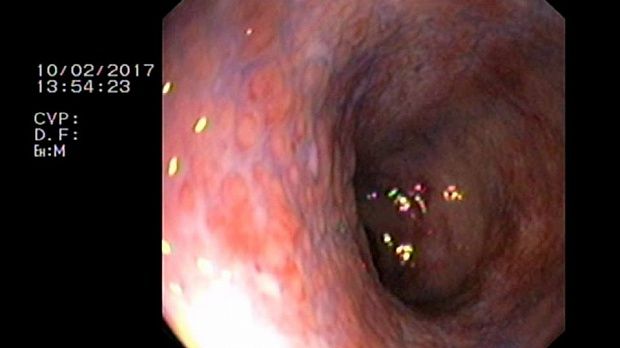

- Атлас

2 мл ( это мин сум, а мы делаем до 10 мл 3% перекись+200 мл физ раствора